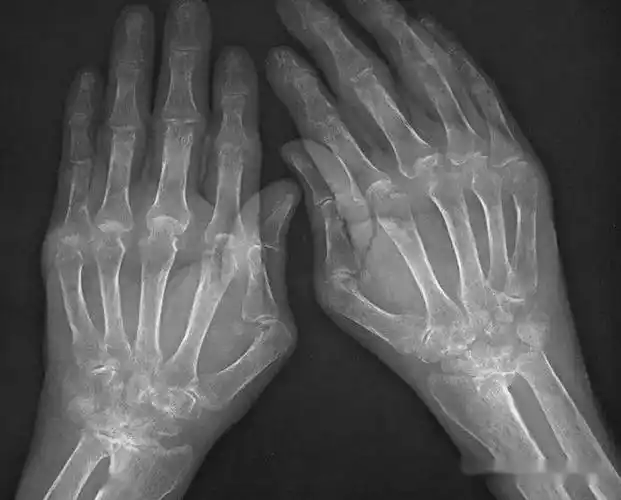

手指关节疼痛,肿胀,关节内有骨性增长物(骨刺).